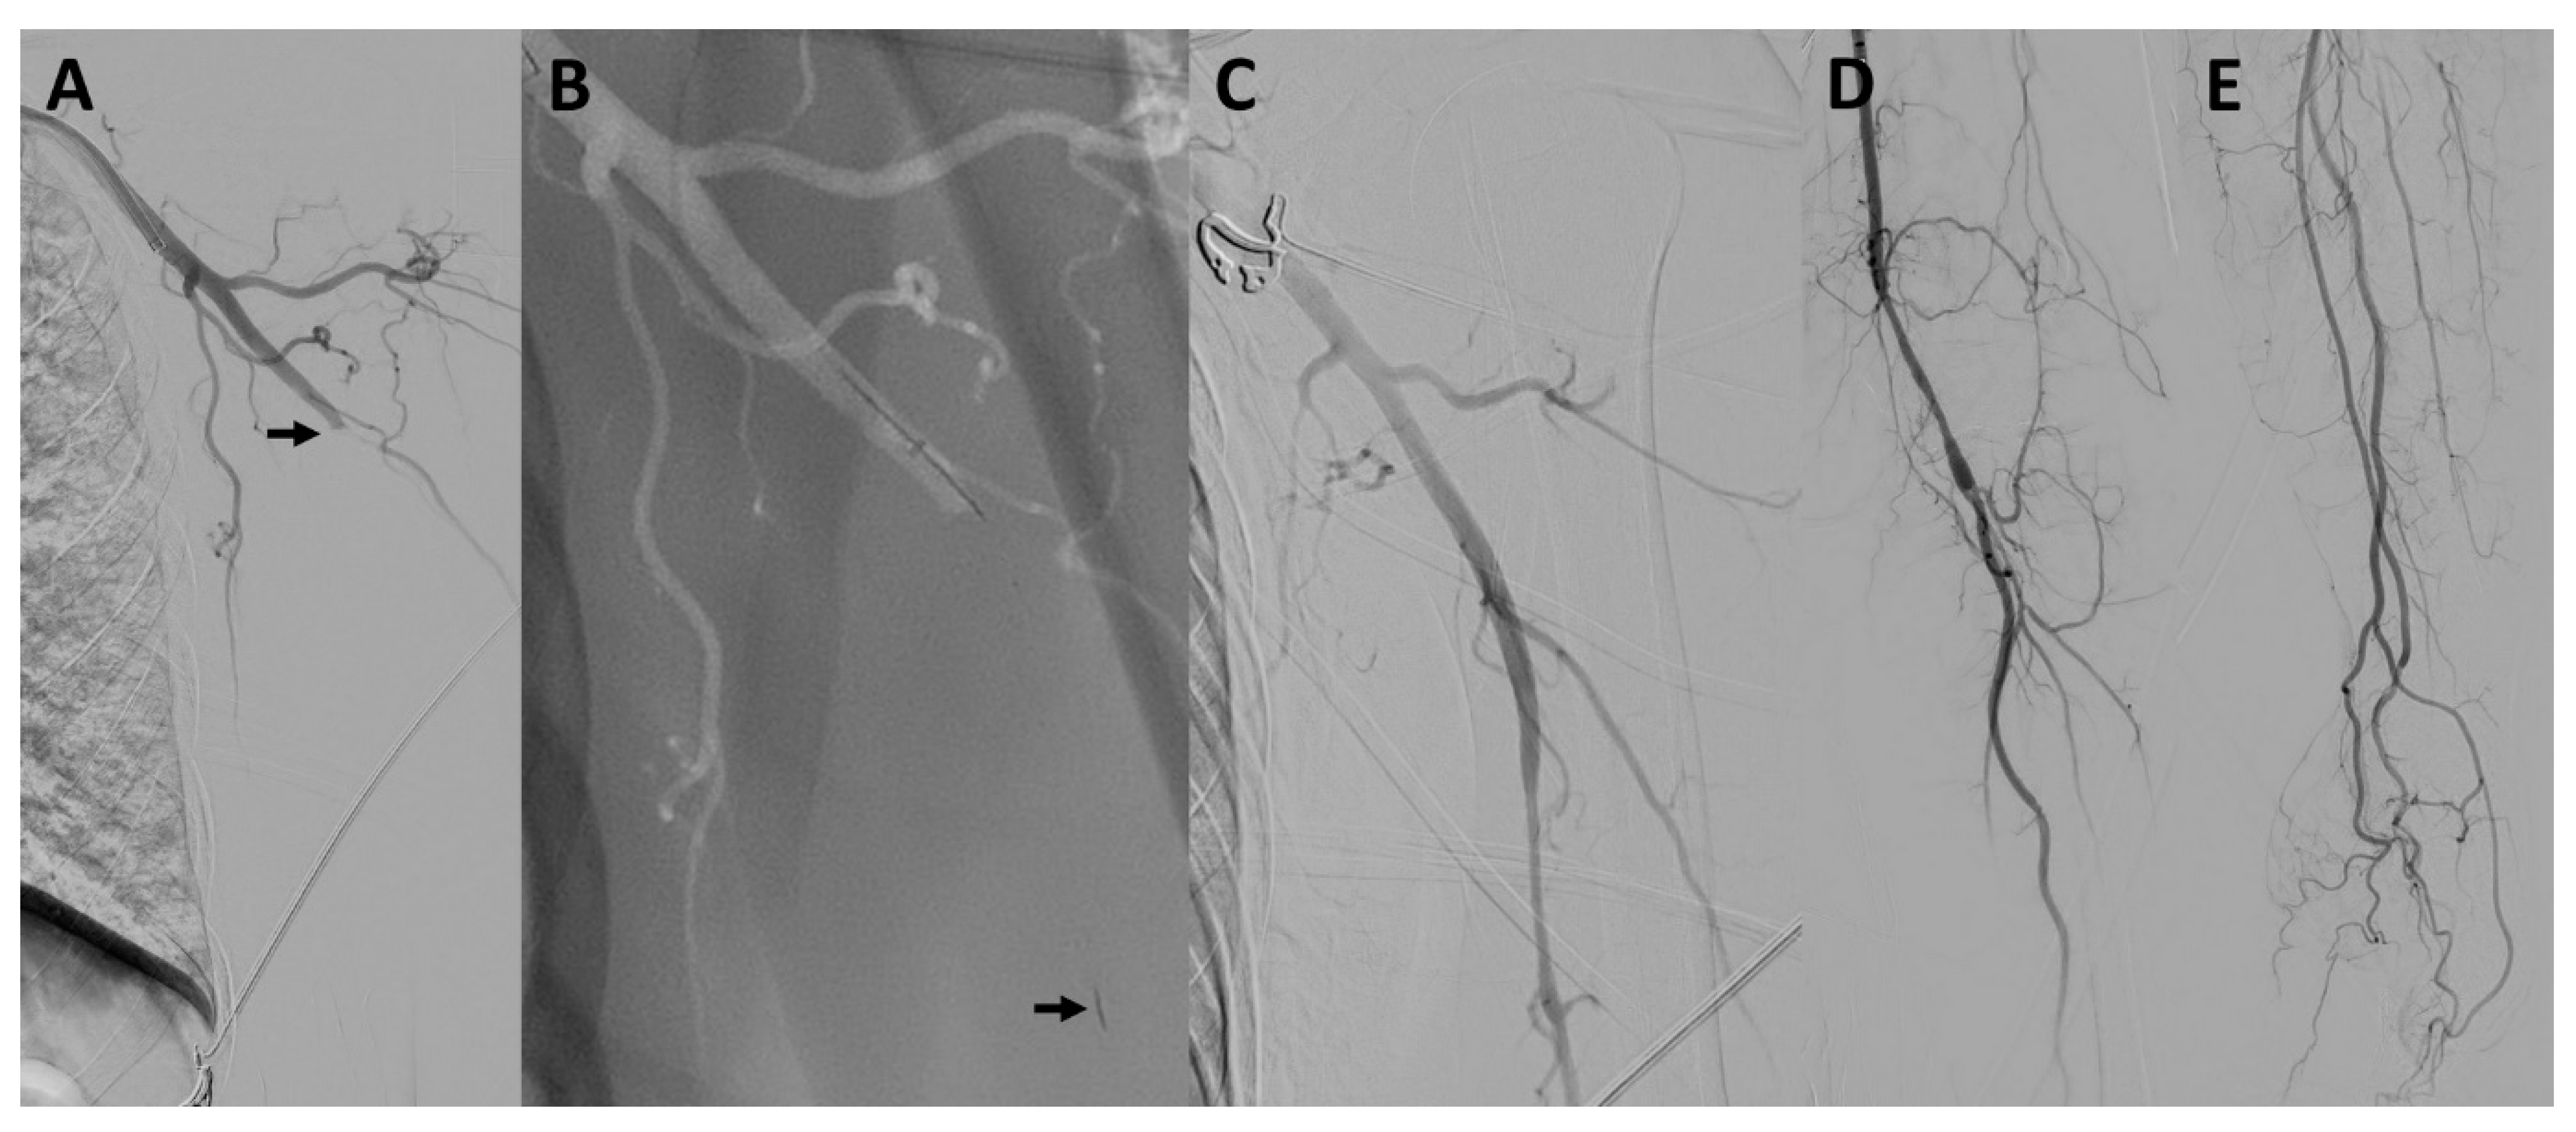

Concomitant Acute Ischemic Stroke and Upper Extremity Arterial Occlusion: Feasibility of Mechanical Thrombectomy of the Upper Limb Using Neurointerventional Devices and Techniques

3. Results